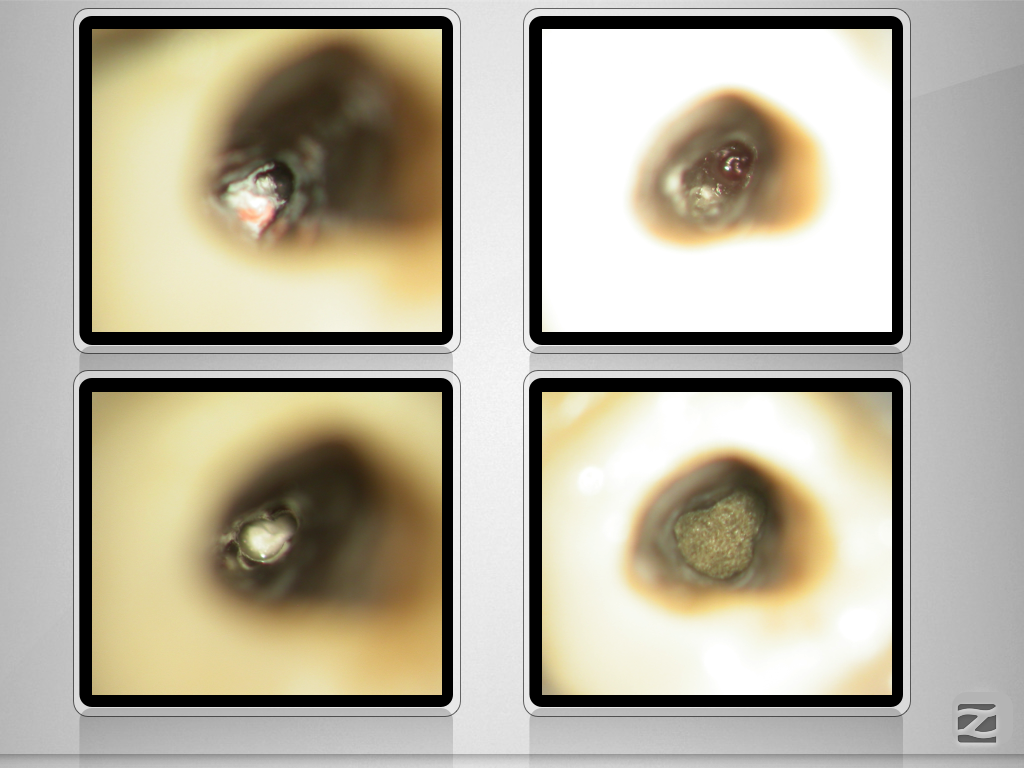

45D.005

1024 × 768

2D vs. 3D (XXXI)